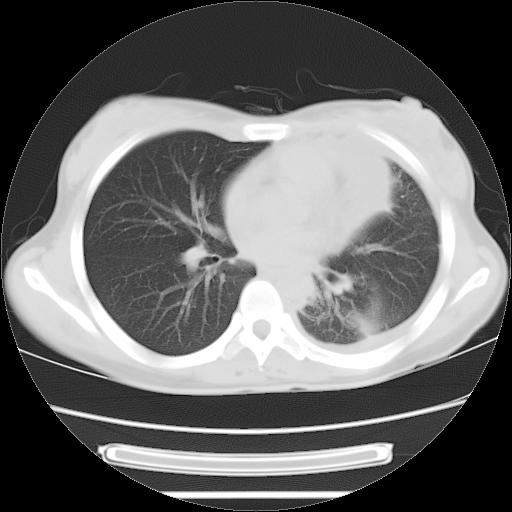

女,29岁,胸部不适,在外院胸片提示胸腔积液,到我院ct检查。

肺窗:

1、左侧包裹性积液伴叶间积液 2、右肺多发结节考虑增殖结节

考虑:1.两肺tb;2.左侧胸膜炎、胸腔积液。

考虑两肺结核,左侧包裹性积液,叶间积液。

右肺多发结节。左胸腔多发包裹性积液。